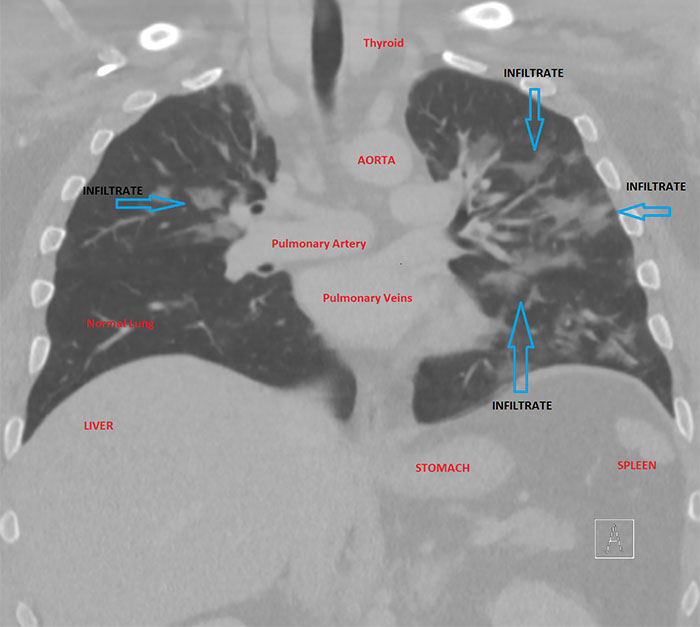

Imgur user and radiologist HeyYoMikey8 said the unknown future is the hardest part of the coronavirus pandemic. HeyYoMikey8 believes it is our own responsibility to educate ourselves so we can all do our part during these difficult times. So, to make it easier for us, the health professional shared what they’re seeing in cases of Covid-19 radiographically. The comprehensive commentary, as well as images used to help in the diagnosis and managing complications or evaluating the progression of the disease, should definitely broaden your understanding of what we’re all facing.

Interestingly, in the early days of the coronavirus outbreak, radiological imaging was not regarded as a way to confirm evidence for COVID-19 cases. Instead, authorities relied on a positive result of the PCR nucleic test. The supply of the PCR test kits, however, was limited and getting back the results took a long time. So, Chinese health authorities soon recognized these difficulties and changed the diagnostic strategy in their 5th edition of the Guidelines on Diagnosis and Treatment of COVID-19. As a result, radiological features of COVID-19 were included as one of the three determinant clinical manifestations to confirm a suspicious patient. The high efficiency, reliability, and accessibility of the radiological diagnostic technology have helped tremendously in identifying the disease. These processes were soon enhanced further by the introduction of artificial intelligence (AI) algorithms.

This could mean CT scanners were to be shut down for up to an hour after a single scan, severely limiting throughput for other patients including for emergent indications like trauma. “The radiology technologists are the real unsung heroes in all of this as they have to deal directly with many potentially infected patients to get their imaging done timely and appropriately, and should be seriously commended right now. We face problems with the diagnosis because a negative study does not rule out the disease, as it may have not yet manifest as an infiltrate despite the infection being present (false-negative scans).”

“Secondly, although certain concerning patterns suggesting COVID-19 on imaging have emerged, all findings are strictly nonspecific and therefore do not entirely rule in the diagnosis, and require additional confirmation as it could still be other entities such as Influenza pneumonia.”

“Finally, all radiology is a business like any other, and we have canceled or deferred almost all elective imaging procedures to help stall the spread of infection and make room for a potential surge of COVID-19 cases,” the radiologist explained. “Therefore, our imaging volumes have dropped by upwards of 50% basically overnight, leaving us with a lack of work for our normal staffing (requiring forced vacations) and a large dip in revenue which jeopardizes our ability to pay the bills and keep our nonphysician employees employed and paid. I do think radiology has helped us at least in this early stage to identify many presumptive cases that were not being considered as COVID-19 at their presentation … It may be helpful for follow up evaluation for potential complications such as ARDS or pleural effusions. Also, there are patients with respiratory symptoms now concerning COVID-19 that have imaging findings/patterns more consistent with other etiology such as bacterial pneumonia or pulmonary embolism, therefore helping to rule out many cases and guiding other appropriate treatment.”